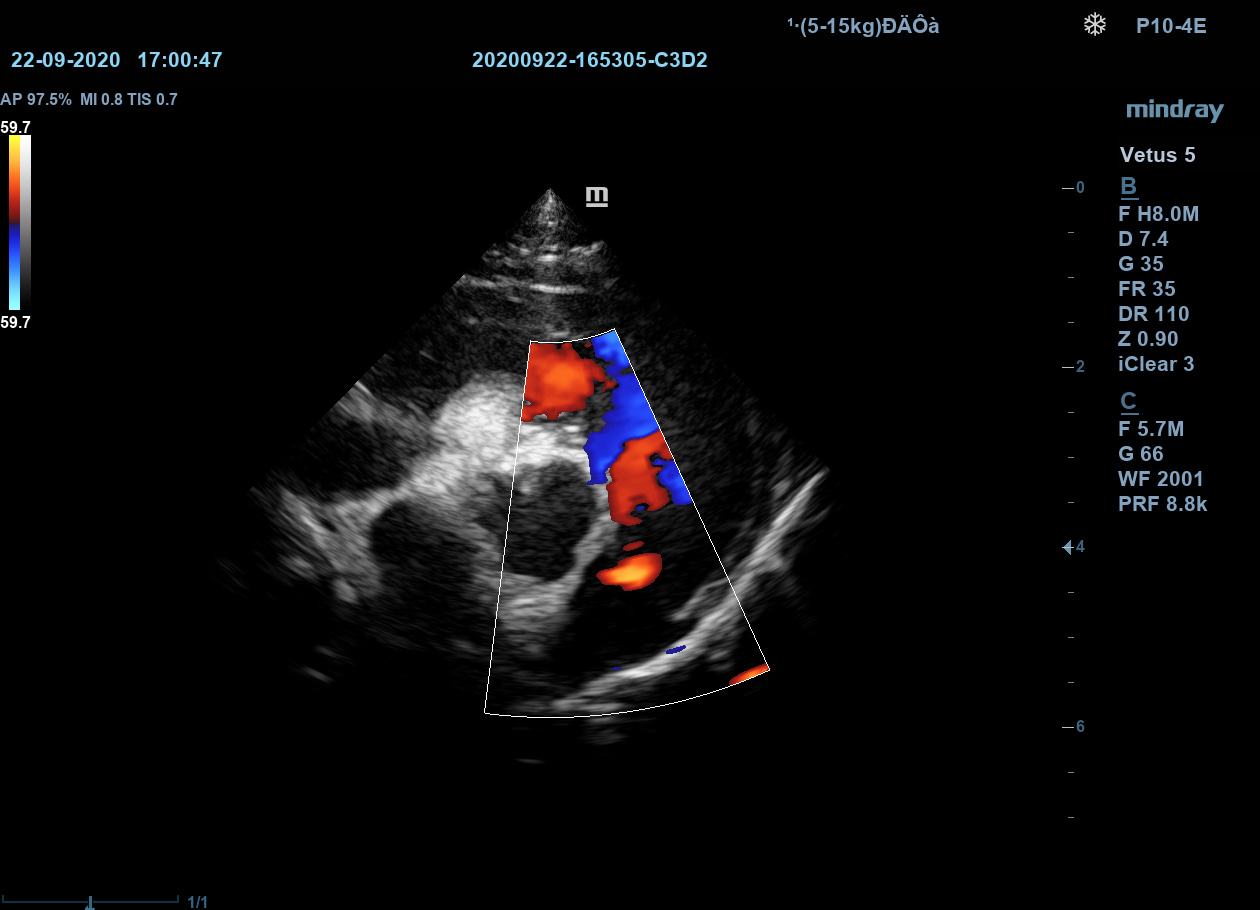

iTouch

Автоматическая оптимизация изображения. При помощи одной кнопки врач узи диагностики получает автоматическую настройку необходимых параметров для улучшения визуализации исследуемого объекта. Оптимизация изображения работает как в B-режиме, так и в режимах ЦДК, ЭДК и PW.

iTouch

Автоматическая оптимизация изображения. При помощи одной кнопки врач узи диагностики получает автоматическую настройку необходимых параметров для улучшения визуализации исследуемого объекта. Оптимизация изображения работает как в B-режиме, так и в режимах ЦДК, ЭДК и PW.